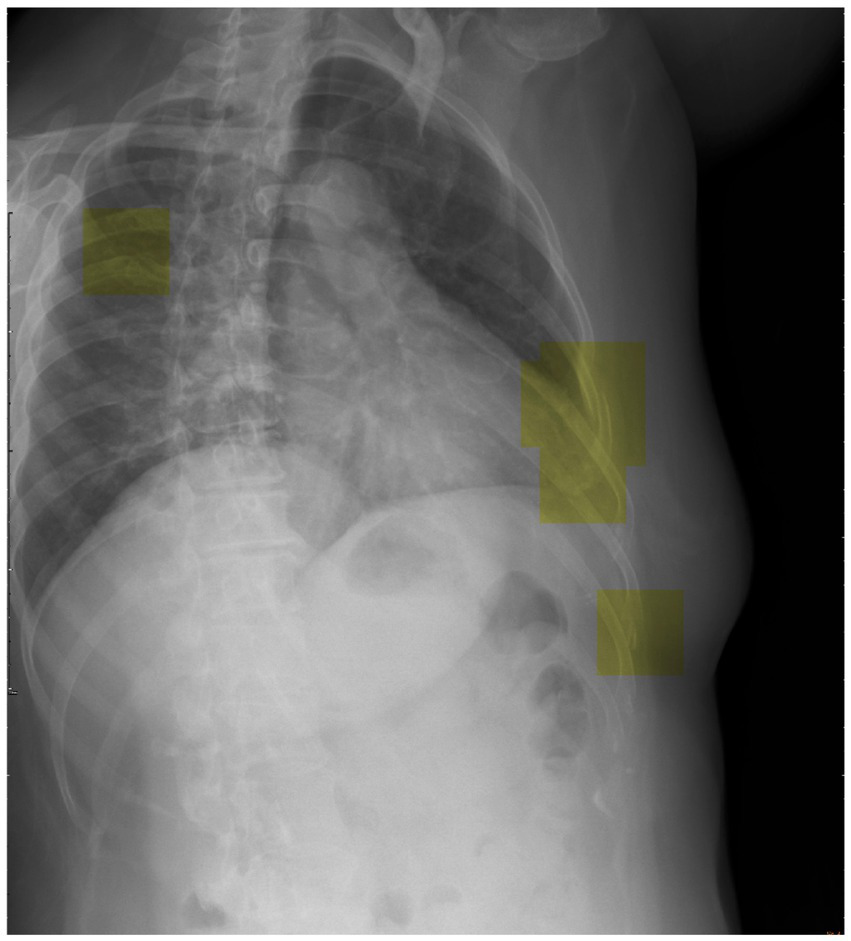

To advance future research efforts, we should endeavor to implement the trained DCNN model utilizing a patch-based sliding window scanning method (43, 44) to interpret chest radiographs obtained from trauma patients in an emergency setting and highlight the suspected fractured ribs. Therefore, we have the opportunity to deploy this advanced tool as a computer-aided diagnostic system in the clinical setting, effectively preventing instances of misdiagnosis. Moreover, we provide a visual depiction (Figure 6) that highlights the utilization of inference (represented by the yellow box) in our model for the detection of potential rib fractures on chest radiographs.

Figure 6

Visual representation showcasing the application of inference (highlighted by the yellow box) in our model for detecting potential rib fractures on chest radiographs.